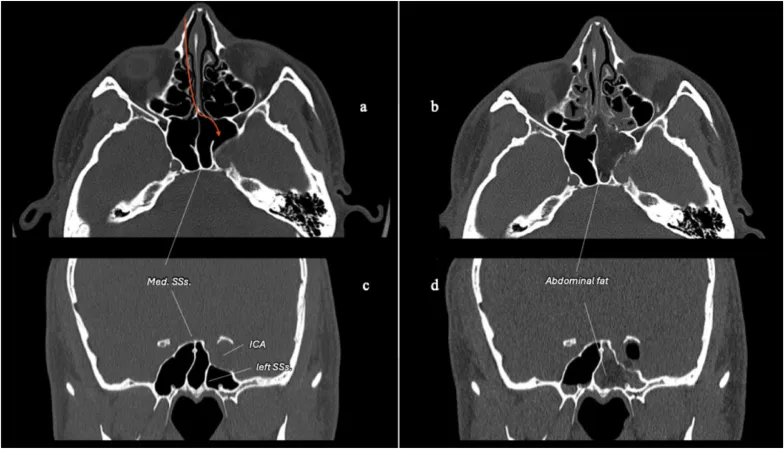

图5:术前及术后轴位、冠状位骨窗CT扫描,展示采用右侧对侧单鼻孔内镜经鼻入路处理左侧海绵窦病变。术前扫描显示蝶窦中隔位于中线,左侧蝶窦间隔附着于左侧颈内动脉海绵窦段隆起。这些间隔是重要的蝶窦内解剖标志。术后扫描显示,通过左侧经鼻甲前部通道,仅进行了左侧半蝶窦切开。鞍旁迷你骨窗已重建,左侧半蝶窦用腹部脂肪填塞,鼻甲前部粘膜已缝合。鼻腔解剖结构得到了最大程度的保留。缩写:Med. SSs.:蝶窦中隔;SSs.:蝶窦间隔。